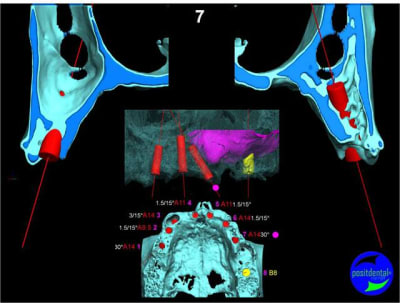

Extraction, pose d’implants Ankylos, pose des piliers Standard définitifs, mise en charge immédiate bi-maxillaire en une chirurgie.

Maxillaire supérieur – extraction 13, 26, 7 implants en MCI, 1 implant en MCR pose summeurs, densification par ostéotme, comblement osseux, bridge provisoire sans fausse gencive avec renfort métallique.

Maxillaire inferieur – extraction 35, 34, 44, 45, 6 implants MCI, comblement osseux, bridge provisoire sans fausse gencive avec renfort métallique.

3D

uniquement le scan pré-op

en attendant la pano voici les coupes de la S.I.A.O.